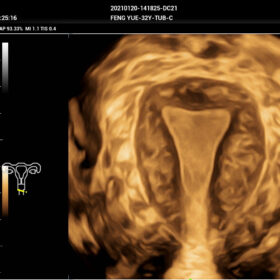

- Smart Scene 3D – Full Stack smartness obstetric solution empowered by ZST+. Comprehensive 3D/4D OB imaging solution with comprehensive fetal parts coverage.

One Key for favorite fetal part imaging, reducing manual adjustment - Smart Face – Automatic removal of occlussions over fetal face with one click

- Smart OB – Accurate auto measurements of most frequently examined parameters BPD/HC/FL/AC/OFD with a single click

- Smart FLC 2D/3D – Automatic Follicle Counting and measurements in 2D/3D mode